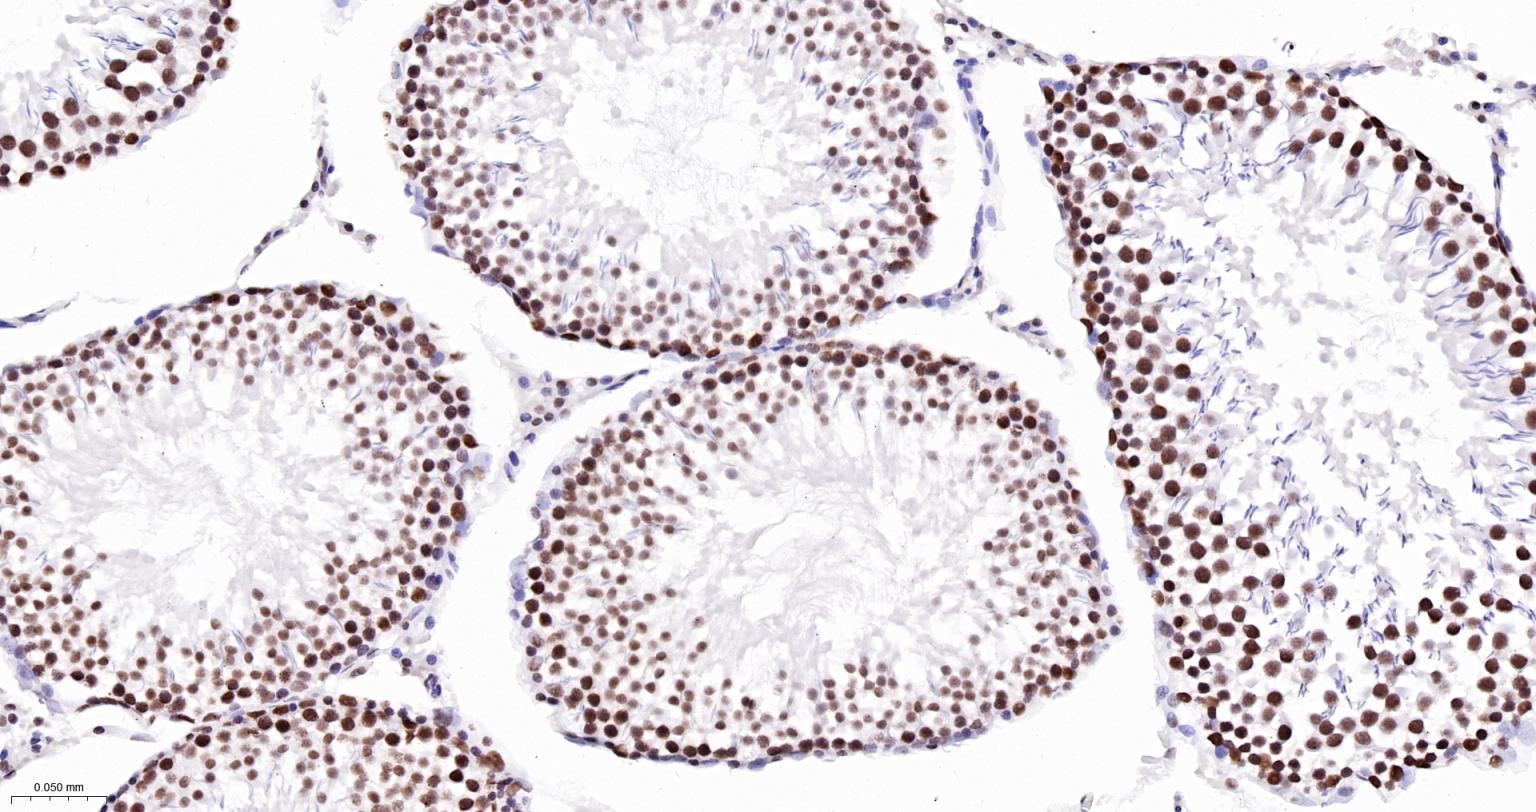

Paraformaldehyde-fixed, paraffin embedded Human Testicles; Antigen retrieval by boiling in sodium citrate buffer (pH6.0) for 15 min; The section was incubated with USP39 Monoclonal Antibody, Unconjugated (bsm-63016R) at 1:200 overnight at 4°C, followed by conjugation to the bs-0295G-HRP and DAB (C-0010) staining.